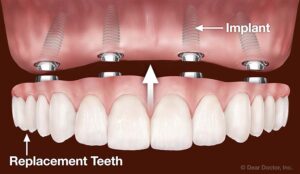

Teeth implants are implanted surgically into your jaw to restore your chewing ability and appearance. These medical devices support artificial teeth like dentures, bridges, or crowns.

Dental implant systems have an implant body, abutment, and fixation screw. The implant body is inserted in the root of your tooth surgically. Then, an abutment fixation screw is used to attach the implant abutment to the implant body. To support the artificial teeth implant abutment extends through the gums.

Teeth implants are the strong foundations for the roots of your teeth. You can either place the fixed replacements or removable replacements on the implants.